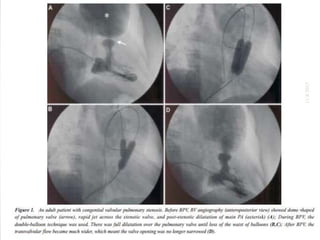

Balloon position and dilation

• Lateral angiogram to be kept as reference.

• Balloon is centered onto the valve and inflated to 6 atm.

• Balloon movement during inflation is common so the catheter must be

maintained in position and the inflation recorded so that it may be

reviewed.

• If no complete resolution of the balloon waist – reposition and the

inflation to be repeated.

• Following dilation the balloon catheter to be exchanged for the wedge

catheter and right heart pull back hemodynamic pressure

measurements to be repeated.

• RV angiogram in AP and lateral projections – dynamic RVOT

stenosis, aneurysm formation or new onset TR..

• Dynamic obstruction will resolve gradually.

11/4/2015

29

30

31